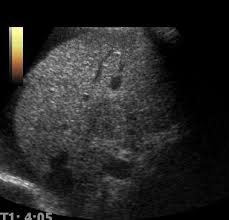

- 지방간